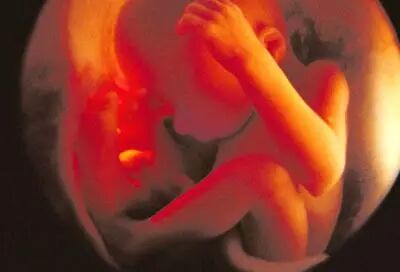

七个月:

脸更清晰了,尽管这么说,但由于皱纹很多,相貌却象个老人似的。如果子宫外有长时间的亮光,他会把头转向光束。他的脂肪层在继续积累,为出生后在妈妈子宫外的生活做准备。